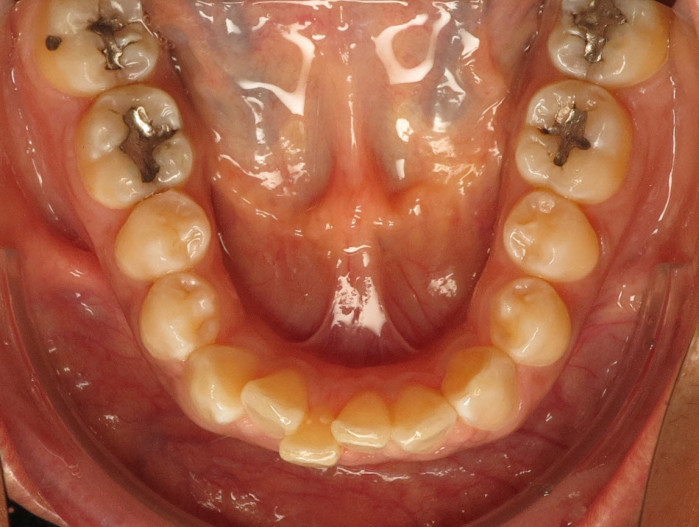

Der intraorale Befund (Abb. 2a–e) sowie die Modellanalyse (Abb. 3a–e) zeigten neben dem Diastema mediale im Oberkiefer vor allen Dingen eine Anteinklination und Supraokklusion beider Fronten. Besonders anterior wiesen beide Zahnbögen eine transversale Enge auf. Dies zeigte sich in einem deutlichen Unterkieferfrontengstand mit Labialkippung des Zahnes 41. Neben Abrasionen und Schlifffacetten, vor allem in der Front, waren auch vereinzelt Gingivarezessionen erkennbar. An Zahn 11 lag eine Schmelzfraktur der Inzisalkante vor. Durch die zwangsgeführte Laterognathie ergab sich eine Mittellinienverschiebung nach rechts von 3 mm. Eine beidseitige Distalokklusion bei vergrößerter sagittaler (6 mm) und vertikaler (5 mm) Stufe war erkennbar. Aufgrund der deutlichen transversalen Zahnbogenenge im Unterkiefer ergab sich links eine Tendenz zum Scherenbiss.